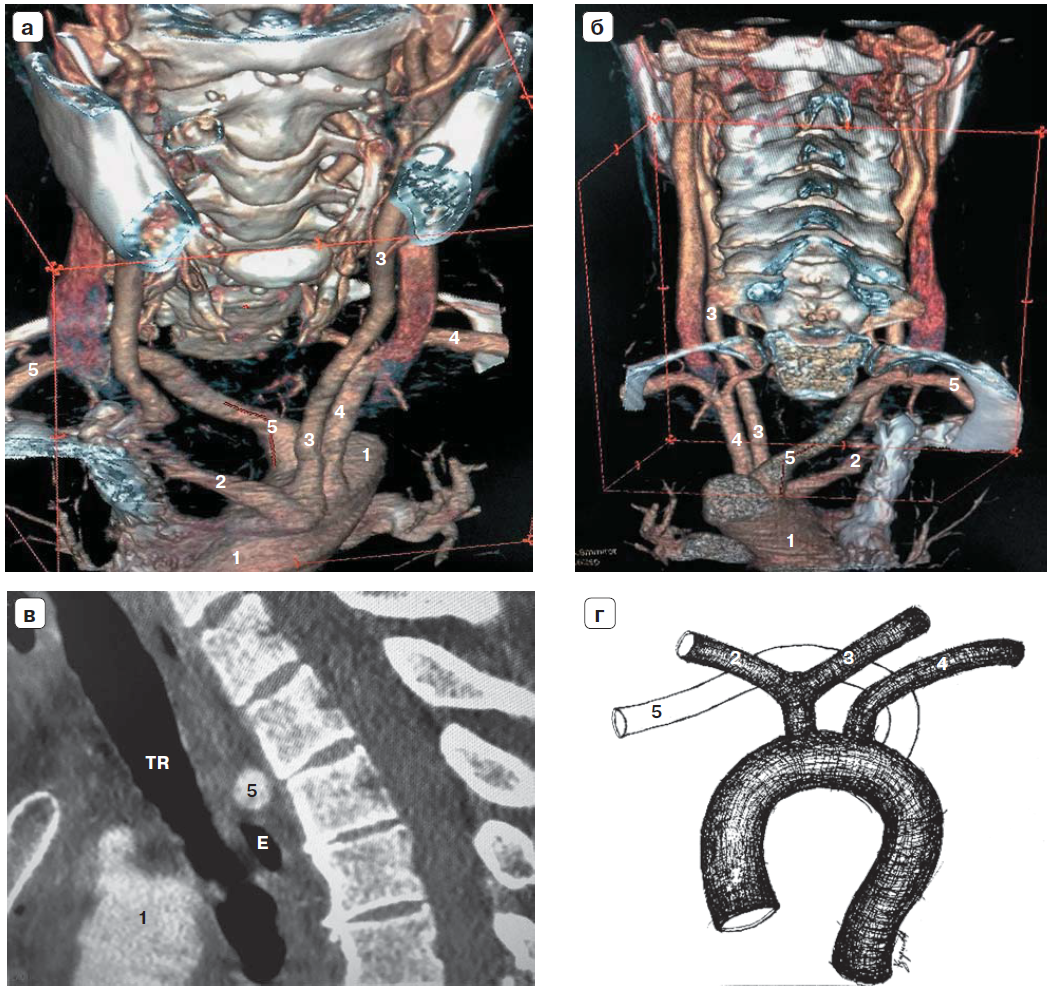

Рис. 3. Компьютерная томография: а – трехмерная реконструкция (вид спереди); б – трехмерная реконструкция (вид сзади); в – сагиттальный срез на уровне срединной линии тела; г – схема: 1 – дуга аорты, 2 – правая общая сонная артерия, 3 – левая общая сонная артерия, 4 – левая подключичная артерия, 5 – a. lusoria, TR – трахея, E – пищевод.

Рис. 4. УЗИ с цветным картированием. Отсутствие Y-признака: а – общая сонная и правая подключичная артерии не объединяются в брахиоцефалический ствол; б – общие сонные артерии находятся в одном направлении (косвенный признак); 2 – правая общая сонная артерия, 3 – левая общая сонная артерия, 5 – a. lusoria, TR – трахея, VBCD – правая брахиоцефалическая вена.